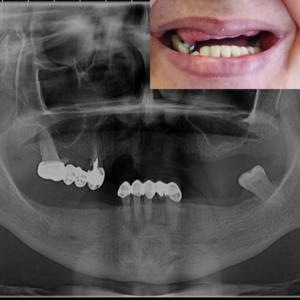

Pacientul se prezintă la o consultație clinică, însoțit de o radiografie panoramică sau un CBCT (tomografie computerizată cu fascicul conic). În cadrul acestei consultații, se efectuează o examinare detaliată și se analizează imaginile pentru a planifica cu precizie tratamentul. Se stabilesc pozițiile optime pentru implanturi și se evaluează starea osului sau a dinților ce urmează să fie extrași, dacă este cazul. Toate datele obținute sunt integrate într-un plan digital personalizat, care asigură o intervenție sigură și eficientă.

Sub anestezie locală sau sedare, medicul dentist plasează implanturile dentare în osul maxilar sau mandibular. Dacă este necesar, în cadrul aceleiași intervenții se efectuează adiții de os sau extracții dentare. Implanturile de tip All on 4 sau All on 6 sunt poziționate strategic, conform planului stabilit în etapa de evaluare, fiind plasate la unghiuri optime pentru a asigura stabilitatea și integrarea lor. Procedura este nedureroasă și are o durată de aproximativ 1 oră și 30 de minute pentru o arcadă, iar pentru ambele arcade poate dura până la 3 ore.

La 24-48 de ore după intervenție, pacientul revine pentru fixarea danturii provizorii pe implanturi. Lucrarea temporară este ajustată pentru a se potrivi perfect și pentru a asigura un zâmbet estetic și funcțional imediat. Această proteză temporară va fi purtată timp de aproximativ 6 luni, perioada necesară vindecării implanturilor. În această etapă, medicul oferă și instrucțiuni post-operatorii detaliate pentru îngrijirea corectă a danturii provizorii și a implanturilor pe durata procesului de vindecare.